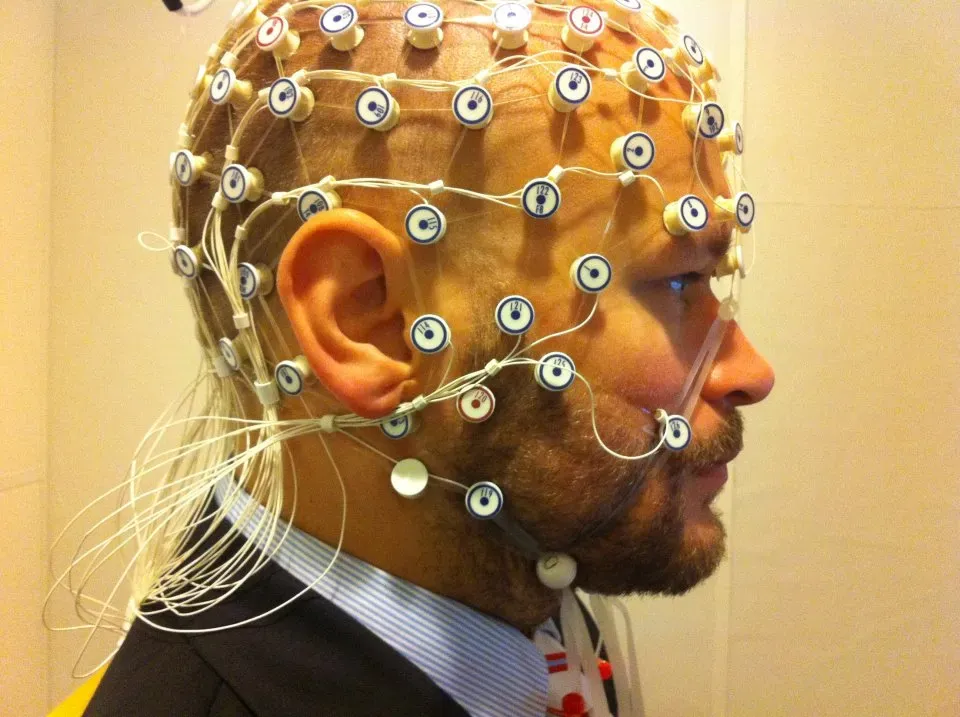

You have probably heard the term “brain waves,” but let’s be real – most people don’t fully appreciate what they represent. The collective activity of billions of neurons produces brain waves, which can be detected using electroencephalography, or EEG. These waves aren’t metaphors. They are literal oscillating electrical fields generated by your brain, and they shift depending on what you are doing, feeling, or experiencing at any given moment.

The level of wakefulness and consciousness can be shown through the frequency of brain’s electrical activity – high levels of consciousness are recorded as rapid waves, especially the beta rhythm, while slow waves such as theta and delta can be recorded during sleep and low brain activity. Studies have shown that gamma waves, the fastest type of brain waves, are linked to higher consciousness and deep thinking. So the next time you feel “in the zone,” that electric feeling is quite literally electric – a measurable surge in your brain’s oscillatory activity.